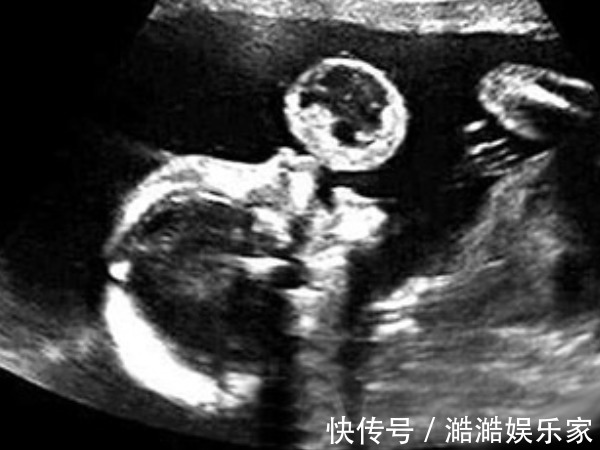

众所周知,怀孕是一件很难的事,在怀孕的前三个月中,许多人会恶心和呕吐,无法进食。怀孕期间这些不适的反应给许多怀孕的母亲带来了麻烦。很多时候,桌上都摆着一桌美食,但根本没有胃口。但并非所有怀孕的母亲都会有妊娠反应,一些怀孕的母亲在怀孕期间没有反应。除了腹部越来越大以外,没有不适的感觉。

实际上,怀孕后,有些人会继续呕吐,而另一些人从未呕吐,其原因直接与未出生的婴儿有关。在现实生活中,许多孕妇都会有妊娠反应,通常每个人都会认为妊娠反应是正常的。1.孕吐少,胎儿发育稳定许多怀孕的母亲发现他们怀孕后根本没有反应。和平时期没有区别,如果不是去医院确认怀孕。您可能不相信自己在怀孕。那么为什么没有怀孕反应呢?医生说:没有怀孕的事实仅意味着腹部的婴儿发育良好且稳定。因此,怀孕期间的反应非常强烈,表明腹部的婴儿相对不稳定。因此,在怀孕期间没有反应的怀孕母亲说,腹部的婴儿发育良好且非常稳定,这是非常受欢迎的事情。

2.激素变化很大,孕吐严重为什么有些怀孕的母亲在怀孕时会感到恶心?这是由于荷尔蒙的大量变化,因为荷尔蒙的变化会导致失衡,从而在怀孕期间引起更大的反应。但是对于每个人,变化的幅度和速度是不同的。一些孕妇的激素水平稳定,波动幅度和速度不明显,这不容易引起孕吐。